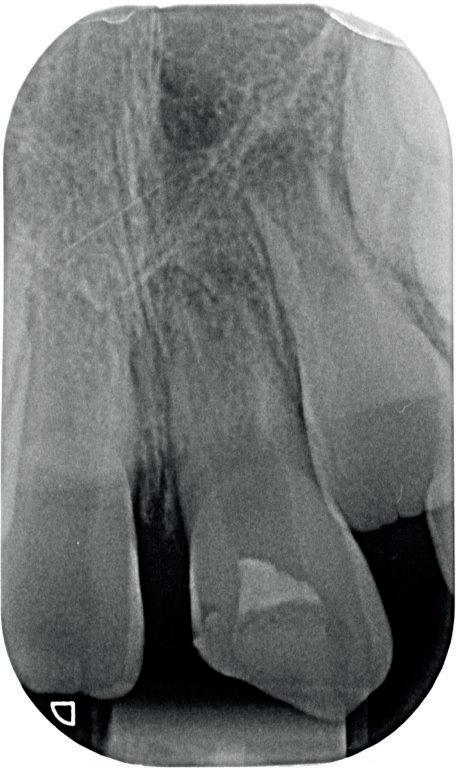

4. Met een LN-boortje zoek ik het instrumentje op en ik verificeer de correcte positie van de toegang.

5. Het afgebroken instrument is verwijderd en het mesiobuccale kanaal is weer toegankelijk.

6. Klinische opname waarop het oorspronkelijke verloop en de positie van het afgebroken instrument te zien zijn. Het instrument was in de wand ‘geschroefd’. Door de te kleine opening moet het ‘roterend’ instrumentarium onnodig veel buigen en komt er veel druk op de vijl

staan, waardoor ze makkelijk kunnen breken. Zorg voor een ‘straight line access’ ofwel een rechte toegang.

7. Hierop is nog eens de correcte opening te zien. Ik heb veel van het aanwezige amalgaam weggenomen om zoveel mogelijk ruimte te krijgen. Ook is te zien hoe ik het mesiobuccale kanaal heb moeten verbreden om bij het instrument te komen. Het palatinale kanaal is niet zichtbaar op deze afbeelding.